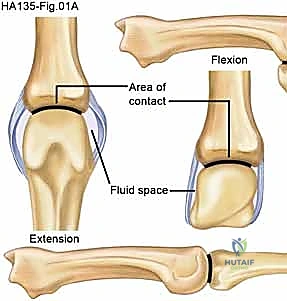

The metacarpophalangeal joint is a condyloid joint, and its osteology allows biaxial motion, facilitating flexion, extension, abduction, adduction, and circumduction. The articular surface of the metacarpal head is highly asymmetric. It features a relatively flat mediolateral convex arc, which governs abduction and adduction, and a much larger anteroposterior convex arc that dictates flexion and extension. Crucially, this articular cartilage extends further volarly than dorsally, and the metacarpal head is substantially wider at its volar aspect compared to its dorsal aspect.

This specific geometry creates the classic "cam effect" of the metacarpal head. The proper collateral ligaments originate from a dorsolateral tubercle on the metacarpal head and insert on the lateropalmar edge of the proximal phalangeal base. Because of the cam effect and the eccentric, dorsal origin of the collateral ligaments, these ligaments are relatively lax when the joint is in extension (allowing for maximal abduction and adduction) and become maximally taut when the joint is flexed to 70 to 90 degrees. If the MCP joint is immobilized in extension, the proper collateral ligaments undergo adaptive shortening and dense collagen cross-linking. Subsequent attempts at flexion are mechanically blocked by these contracted, fibrotic ligaments.

The MCP joint is enveloped dorsally by a relatively loose, redundant capsule that inserts onto the ridges surrounding the articular cartilage. The volar plate of the MCP joint is a fibrocartilaginous extension of the phalangeal articular surface. Unlike the volar plate of the proximal interphalangeal joint, the MCP volar plate is highly collapsible and membranous proximally, demonstrating very little tendency to produce fibrotic checkrein ligaments. This anatomical distinction is the primary reason why MCP joint flexion contractures are rare.